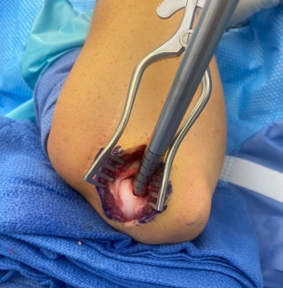

Arthroscopic examination of an OCD lesion

The damaged cartilage and underlying bone is removed using appropriate sizers